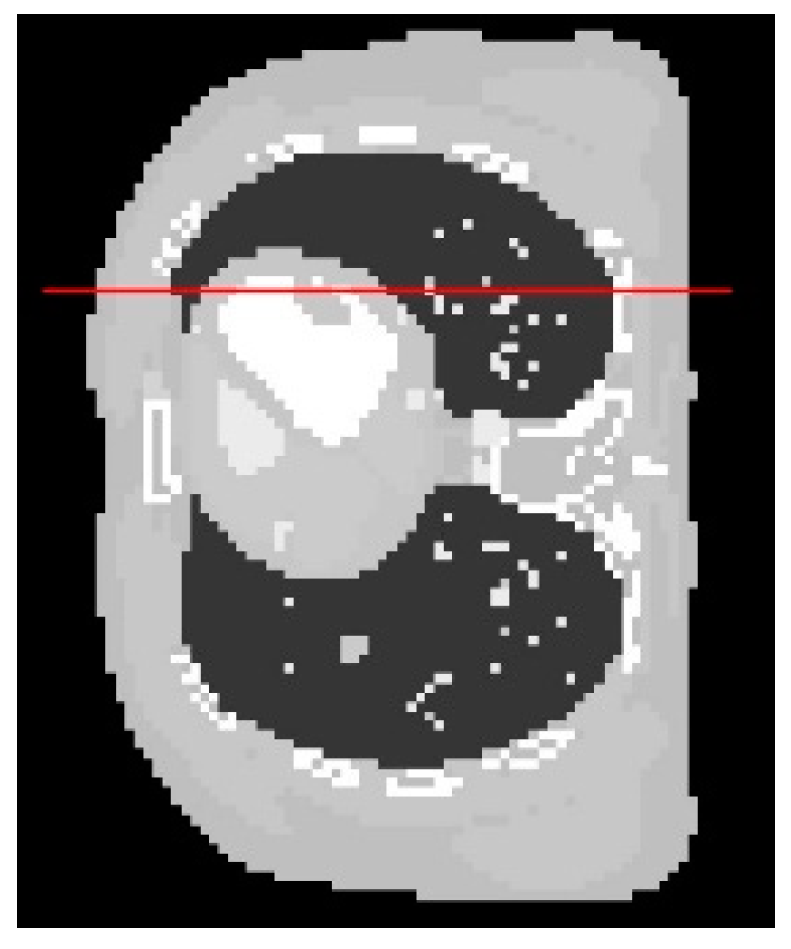

From a visual inspection of Figure 4, the reconstructed image from the proposed algorithm and the cross-validation method are rather similar to each other. Not much outstanding difference can be observed in the images from both cases. However, they are ones that are the most similar to the exact phantom image, as they contain sharper edges than the blurry result from the arbitrary setting. Even though the CGLS algorithm is able to recover small features as well as edges, the image is relatively noisy compared to the result from the proposed algorithm and the cross-validation method. To make a comparison clearer, we analysed one-dimensional profile plots of all the results along an arbitrary row of a cross-sectional slice as shown in Figure 5. The 1D plot of all the results is shown in Figure 6, in comparison with the reference exact phantom.

Figure 5.

The image profiles of all the results along the horizontal line are plotted. The display window is [0–0.02].